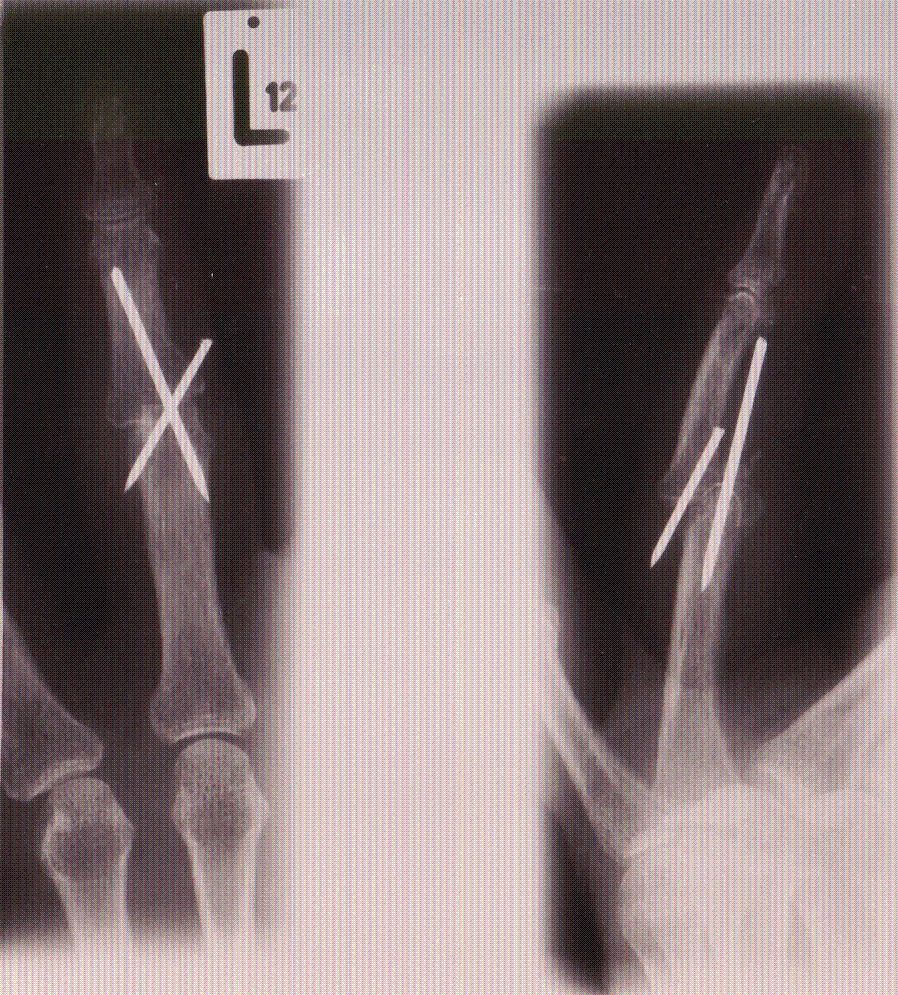

Operation - offene Reposition und 2-fach gekreuzte K-Drahtung

Die operative Versorgung entsprach nicht den anerkannten Standards der Unfallchirurgie. Die Fraktur und die Luxation im Gelenk wurden nicht beseitigt, die Fragmente nicht exakt fixiert, es wurde auch keine suffiziente temporäre Arthrodese (operative Gelenkversteifung) ausgeführt. Die Kirschnerdrähte waren deutlich überstehend und konnten deshalb zu Reizungen im umliegenden Gewebe und zur Fast-Perforation der Haut führen.